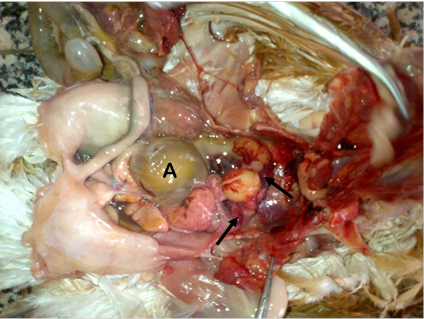

The gross lesions observed at postmortem were congested comb and wattles (30.00%), prolapsed vent (40.00%) and pale carcasses (100.00%) in addition to pale, friable and ruptured liver (100.00%), cardiomegaly (10.00%) and renomegaly (10.00%). Others were congested spleen (10.00%), congested lungs (100.00%), frothy exudation within the trachea (20.00%), congested and ruptured ovarian follicles (100.00%) and shell-less eggs within the oviduct and/or abdominal cavity (100.00%) as shown in Figure 1.

Figure 1 The abdominal cavity of a pullet diagnosed of mixed bacterial infection on a layer flock in Masaka, Nasarawa State, Nigeria. Note the congested and ruptured ovarian follicles (arrows) and shell-less egg within the abdominal cavity (A).